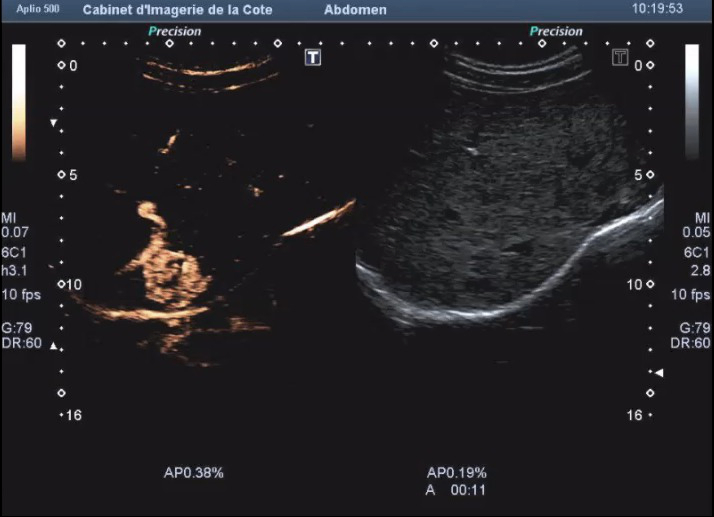

Échographie de contraste

Il s’agit d’une méthode d’imagerie associant l’échographie conventionnelle à une injection intraveineuse d’un agent spécifique de contraste permettant une étude dynamique de la vascularisation organique ou lésionnelle. Les agents de contraste utilisés sont des microbulles d’environ 3 microns gardant un caractère intravasculaire strict (Sonovue®Bracco).

Nous utilisons l’échographie de contraste surtout pour caractériser les lésions hépatiques, afin d’éviter dans la mesure du possible des examens IRM ou scanner. Ceci permet aussi souvent de réduire la période angoissante entre la découverte d’une lésion et son diagnostic. L’injection de contraste permet également d’augmenter la sensibilité de l’échographie lors de la recherche de métastases hépatiques ou de néoplasie hépatique secondaire à un cirrhose.

Les contre-indications médicales à l’injection sont une cardiopathie ischémique instable et un antécédent récent de syndrome coronarien aiguë. Aucun effet secondaire n’a été rapporté (ni néphrotoxicité, ni réaction d’hypersensibilité).